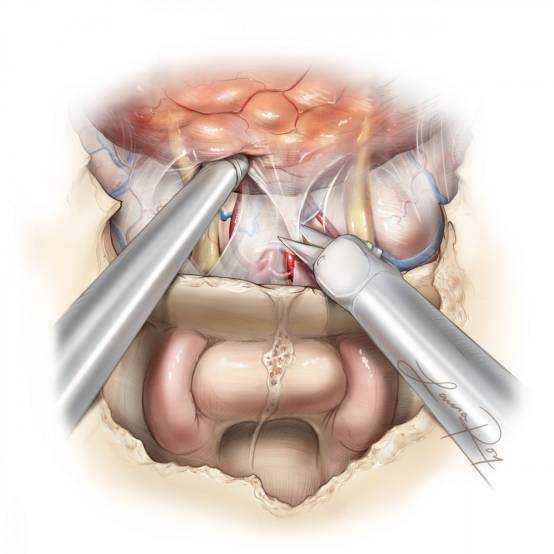

图9. 笔者更喜欢从后向前游离瘤体,这样在手术早期可以清楚的看清A1分支。精心处理穿支血管,对于取得理想手术效果至关重要。电凝及切断被包裹的嗅神经理。通常有较厚的蛛网膜包裹保护血管。

图10. 从脑组织上游离肿瘤包膜时,使用小棉片轻柔的擦拭分离脑组织。牺牲嗅球及嗅束。额眶和额极动脉常与肿瘤的上外侧极粘连(手术盲点),在过度牵拉瘤体时通常会不经意的被撕破。

图11. 展示重建前,术腔的视图。笔者通常用45°内镜检查视神经管的内侧,以可靠地排除肿瘤浸润,45°内镜适合这样的目的。